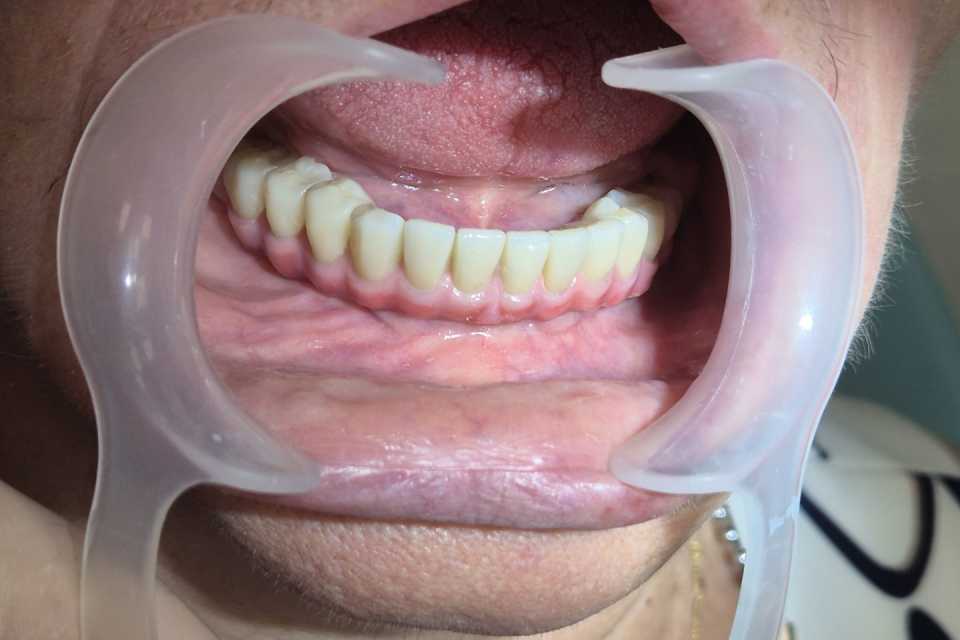

Pacienta, în vârstă de 77 de ani, purtătoare veche de proteză mobilă la nivel mandibular, a dezvoltat o resorbție osoasă severă, ceea ce a dus la dificultăți majore în masticație și imposibilitatea purtării protezei. Se prezintă cu dorința de a beneficia de o lucrare fixă la nivelul mandibulei.

Cu ajutorul a 4 implanturi dentare Mega-Gen AnyRidge, inserate interforaminal (tehnica All-on-4), realizăm o lucrare din ceramică pe suport de titan, formată din 12 elemente, înșurubabilă pe suport multiunit.